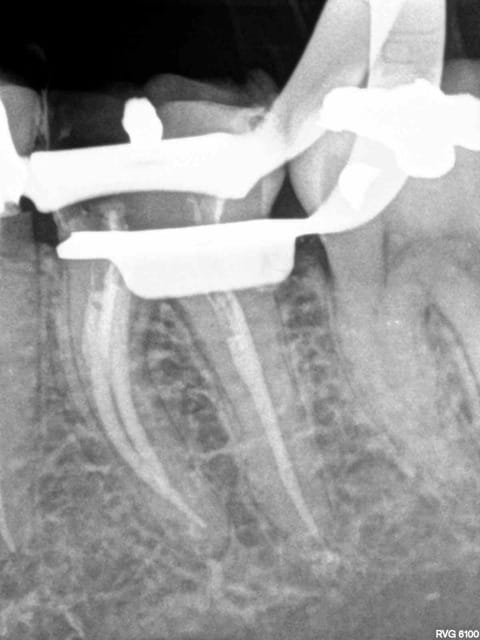

J'aimerais bien qu'on me dise où est l'image péri apicale.

Je me répète, je ne vois qu'un épaississement du desmodonte, autrement dit rien de si alarmant.

De même, on parle de faux canal mais là non plus rien de bien certain avec cette radio. Le trajet de l'obturation en mésial ne semble pas correspondre au trajet de la racine mésiovestibulaire, mais mais la mésiolinguale pourrait bien correspondre par contre. Rien de certain donc, et il faudrait au minimum une radio sous une autre angulation ou alors une imagerie 3D pour être fixé.

C'est clair qu'il'est difficile de voir une image péri apicale sur une radio où on ne voit pas le péri apex. D'un autre côté notre jeune débutant victime nous parle quand même de parodontite apicale et qui plus est aigue. On parlera donc ici de parodontite sans atteinte parodontale. Je pense que le gros orteil est touché.

On n'oubliera pas que seules les deux tiers des images apicales radioclaires seraient visibles sur une rétro alvéolaire DE BONNE QUALITE. La moitié sur une pano.

Par contre il existe clairement une amorce de faux canal et création de butée. Sinon notre jeune victime aurait trouvé le conduit béant plus après. Faut être miro ou politique ou syndicaliste pour affirmer le contraire.

Au vue de la radio j'ai l'impression qu'il ne s'agissait pas d'une calcification mais d'une fausse route due à une probable utilisation d'un HeroShaper. Après je pense qu'il aurait du t'adresser la patiente à toi si il a un doute afin que tu prennes ta décision d'assumer ou pas pour la suite du travail

Je suis OK avec toi .on dirait que c est obturé nickel mais qui il manque juste un canal a faire ou a finir.

ton obturation en mésial ne va pas à l'apex!

...mais peut-être ne faut-il pas se fier à la radio!